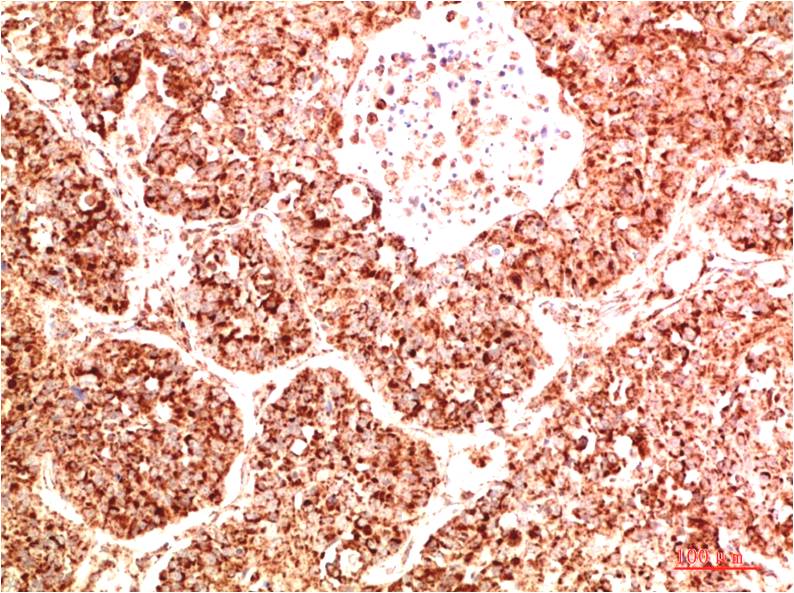

Acetyl P53(K382) Mouse Monoclonal Antibody(5H10)

Applications :IHC

| Recommended dilutions: | IHC: 1:100-200 |

| Specificity: | The Acetyl P53(K382) Mouse Monoclonal Antibody can detects endogenous Acetyl P53(K382) proteins. |